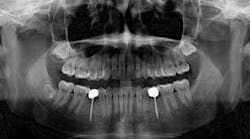

Hygiene. It can be agreed upon that if an implant can’t be kept clean, then the potential for failure and difficulties rise exponentially. A 90-degree angle between the implant and crown is virtually impossible to keep clean and maintain. As amazing as some hygienists are, it is impractical to expect that a curette can get into that space to clean it without making hamburger of the tissue. The implants were cemented on, so they are not easily retrievable. The emergence profile is nonexistent. Do natural teeth look like this? I would submit that when restoring implants, it is our job to mimic the shape and emergence profile of natural teeth as closely as possible. When we don’t, then we lose the inherent cooperation and benefits that the tissue can provide. To help the parents understand this concern, I showed them an example of a traditional implant vs. the “pumpkin on a toothpick” implant. The side-by-side comparison spoke for itself.